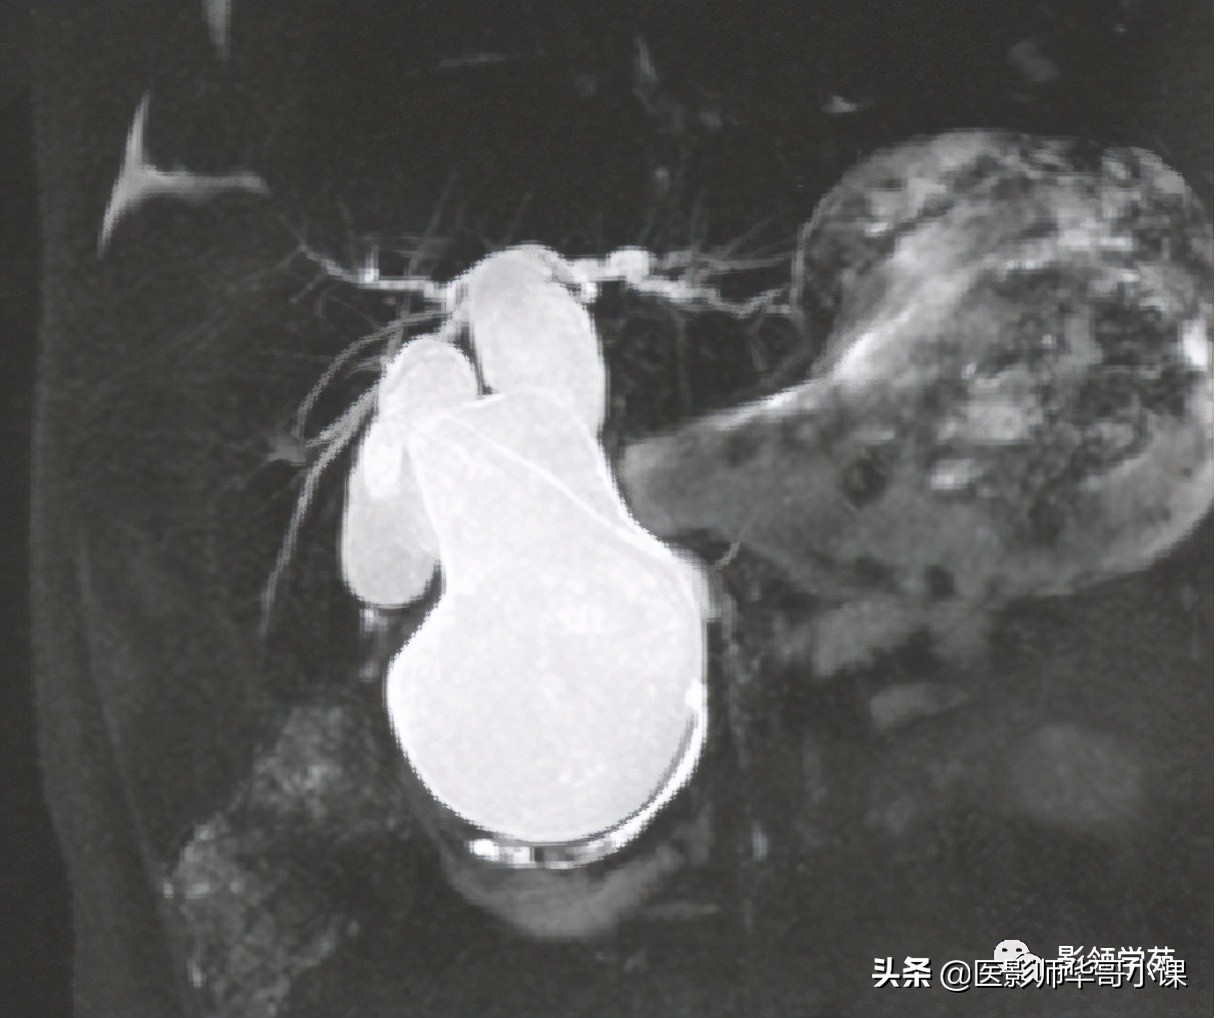

2、“中心点征”是又一重要的征象,是指囊肿阴影内的小点状软组织影像,平扫密度等于或高肝实质,在T2WI序列上呈环状低黑信号,中央区呈圆柱稍高信号,其病理基础是门静脉分支被胆管扩张的囊壁包绕,并在切面上呈轴位投影。Seth等认为“中心点”征象的出现足准确的诊断本病。

磁共振胰胆管造影(MRCP)

- MRCP是一种有效的检查方法,可清楚地了解肝外及肝内胆管的形态。根据重T2 权重序列的静态水(包括胆管和胰管内分泌物)表现为高信号,而实质性器官为低信号,流动的血液因为流空效应而无信号,因而MRCP不需要造影剂就可以获得良好的对比。可显示肝内胆管扩张的部位、大小以及有无结石存在,且有三维结构形态。并可发现本症并不合并胰胆管合流异常,此为与先天性胆管扩张症区别之一。后者可合并肝内胆管的扩张,且几乎均存在胰胆合流异常,而先天性肝内胆管扩张症则不合并胰胆合流异常。Caroli病多无明显的肝外胆管的狭窄和梗阻征象。许多学者认为本法可以作为Carolis病的首选方法。